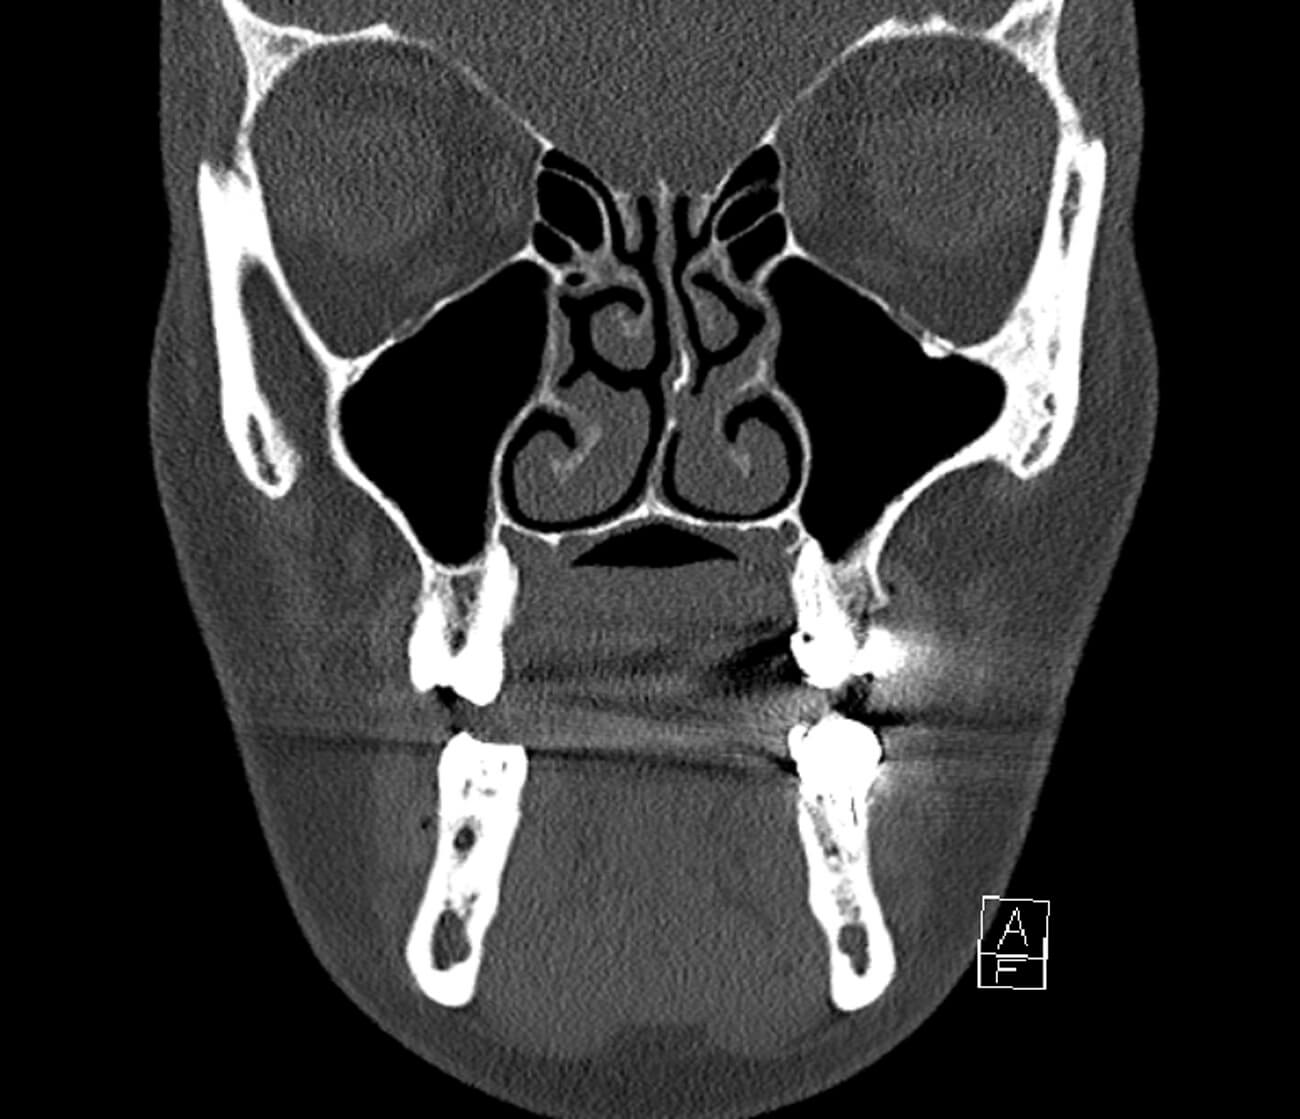

Figure 1b: CT facial bones, brain, sinuses without contrast - thick, bones.

Computed tomography (CT) imaging showed no acute intracranial abnormality with minimal periorbital haemorrhage without evidence of significant optic nerve compression. Despite this, clinical findings strongly indicated OCS, prompting the decision to proceed with an emergency LCC.